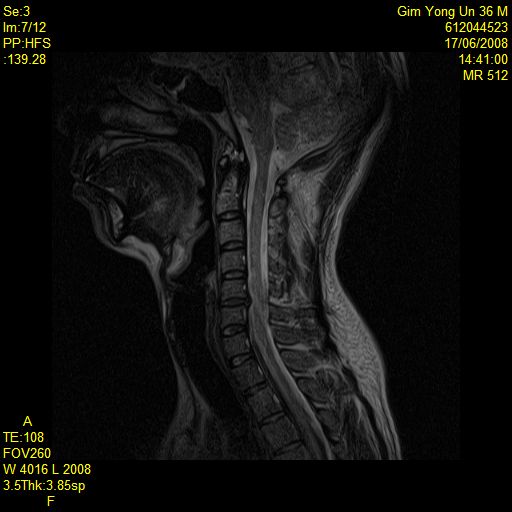

* MRIԴϴ. ǰԴϴ. Ͽ ȭϽñ ٶϴ ūȿ ϼŵ ϴ. (ֹȣ : 23320943ac0e / ī,ͳݹŷ ιȣ : 67545895) , ü Ư Ű 170 Cm ü 63 Kg 38 ȯ ǥغ ôĸε Ǵ ġȿ ū ϼŵ ϴ. ش Ͻø 㿡 ˴ϴ. ǥغ Ӹ ƴ϶ , , Ϗ ٸ Ͽ Ʒ شȯ ȣ˴ϴ. Ư ǥ ǥõ 10 ̳ ų ּȭ ˴ϴ. ǥ ǥõ ȯ̳ ð~ ̳ ȿ ֽϴ. ȯںе鲲 ϰ ü ǥغ ϸ鼭 ȯ ȣ ġ ִ Ȯϰ ֽϴ. ٸ ε ȯ ġϰų ġῡ Ǵ ôĻ· Ÿ μ Ÿ ִ Դϴ. ġᳪ ߹ Ͻô شǴ Ʒ ϼ. IJϰ üũϽø 㿡 ˴ϴ. 1C.ٸǷ, 1C.ٱ (), 2C.پ˷⼺(˷) 2C,3C,ΰ 4C.5C.ھ, հ ̳ , 5C.6C.ڰ հ ̳ 6C. κ Ḳ , 6C.ھ Ḳ , 1T. κ , 6T., 8T. , 10T.ٸǷ, 3L., ũ(߰Ż)ġ, հ , ġ, , Ḳ ġ Ǵ ġ ħ Ƿ ġ ͳ ˻ڷ õ Ѵ (5 ) Ḳ ־ ܰ ġḦ Ÿ Űܰ Ͽ ̸ Կ ũ Ѵ ġḦ Խϴ.. ٰ 6 ° ȿ Ÿ MRI Կ 56 ũ Ű ¦ ִ ¿ 缱 Դϴ... Ѵ ġḦ ƺ ȿ ƿ ؾ ȲԴϴ. 缱Ե ȿ ° ū ؾ ȴٰ ϼ̽ϴ. |